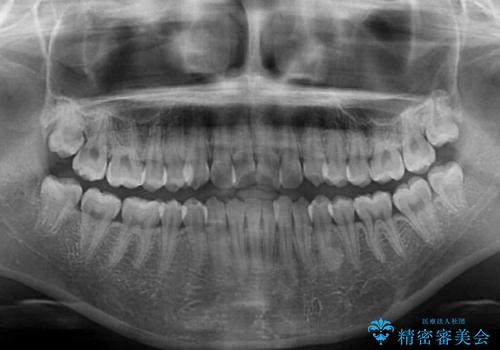

- 口元のデコボコを気にして来院された患者様です。

前歯の捻れにより口元が閉じにくくなっていたため、歯列全体の側方への拡大と、歯と歯の間を少し削ってスペースを獲得することとしました。